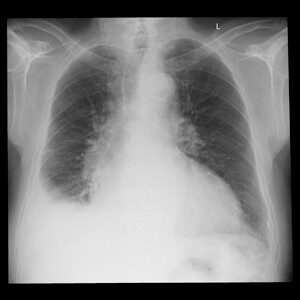

Reale Klinikbilder statt Demo-Grafiken.

Die spezialisierte Lernplattform für Projektionsradiographie. Im Mitgliederbereich steht eine stetig wachsende Fallsammlung mit realen Röntgenbildern zur Verfügung — systematisch aufgebaut, mit strukturierter Befundung, Befundcheck und klinisch relevanten Zusatzhinweisen.